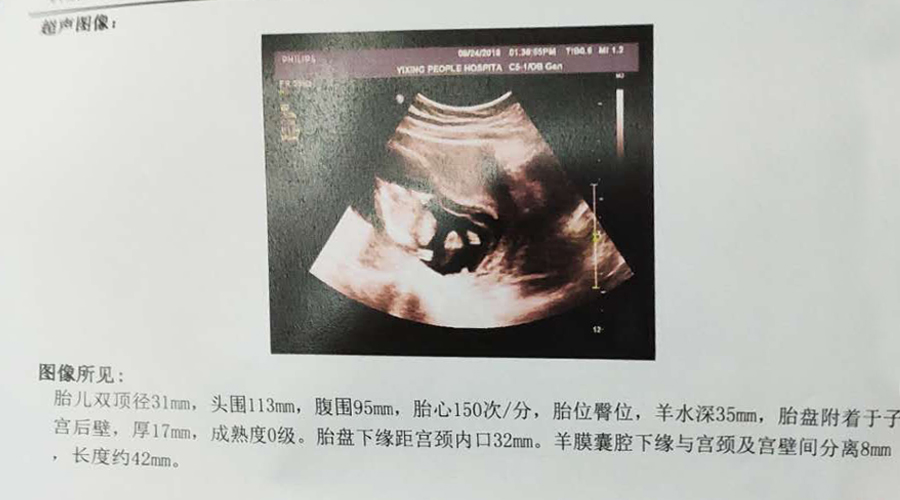

B超显示羊水量正常,听到了宝宝扑通扑通的心跳声,似乎又看到一丝希望,拿着单子跑去医生办公室,那位胖医生还是之前那些话,要求住院做手术拿掉胎儿。沙先森要求转上级医院,然后签了字带着我去了人民医院,沙先森在签字的时候坚定地对着我说人民医院不行的话我们再去无锡。

沙先森请假在医院陪我。每天扎针打黄体酮,挂了两天消炎药改口服,时刻做好清洁工作,血止住了,暗红色变成褐色,住院期间也做了NT检查,一切正常。住了大概十天的样子,虽然因为家里的琐事,和沙先森生气拌嘴,不到五分钟,血又止不住开始流,第二次大出血又开始了,那种前功尽弃的悔恨,自责,内疚......一下子让自己明白了很多,从那以后我再也没和沙先森为了类似的事情拌嘴,理解着他对我的爱,责任,压力和难处。我在内心对宝宝默念了一千遍一万遍对不起......又度过了漫长的15天,血慢慢止住,屁股上留着三十多个针孔,检查定期在做,宝宝发育一切正常,但宫腔内一直存在积液吸收不了。二十多天的住院时间里,每天送往迎来,有保胎的有生孩子的,也有没长胎心来做停止妊娠手术的,看到来生孩子的产妇我特别羡慕,也希望自己能顺利迎接这么一天......

在做羊水穿刺之前去人民医院做了之前预约好的大排畸,除了那顽固的宫腔积液,其他一切正常,胎儿特别调皮,在肚子里像滚筒洗衣机一样翻来覆去,B超医生都忍不住感叹这宝宝真皮,动个不停。此刻的心情是欢愉的,甚至忘记了一周后的羊水穿刺手术。